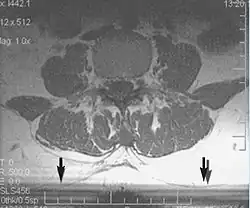

Metal artifacts occur at interfaces of tissues with different magnetic susceptibilities, which cause local magnetic fields to distort the external magnetic field. This distortion changes the precession frequency in the tissue leading to spatial mismapping of information. The degree of distortion depends on the type of metal (stainless steel having a greater distorting effect than titanium alloy), the type of interface (most striking effect at soft tissue-metal interfaces), pulse sequence and imaging parameters. Metal artifacts are caused by external ferromagnetics such as cobalt containing make-up, internal ferromagnetics such as surgical clips, spinal hardware and other orthopaedic devices, and in some cases, metallic objects swallowed by people with pica.[3] Manifestation of these artifacts is variable, including total signal loss, peripheral high signal and image distortion (Figs 3 and 4).[1] Reduction of these artifacts can be attempted by orientating the long axis of an implant or device parallel to the long axis of the external magnetic field, possible with mobile extremity imaging and an open magnet. Further methods used are choosing the appropriate frequency encoding direction, since metal artifacts are most pronounced in this direction, using smaller voxel sizes, fast imaging sequences, increased readout bandwidth and avoiding gradient-echo imaging when metal is present. A technique called MARS (metal artifact reduction sequence) applies an additional gradient, along the slice select gradient at the time the frequency encoding gradient is applied.